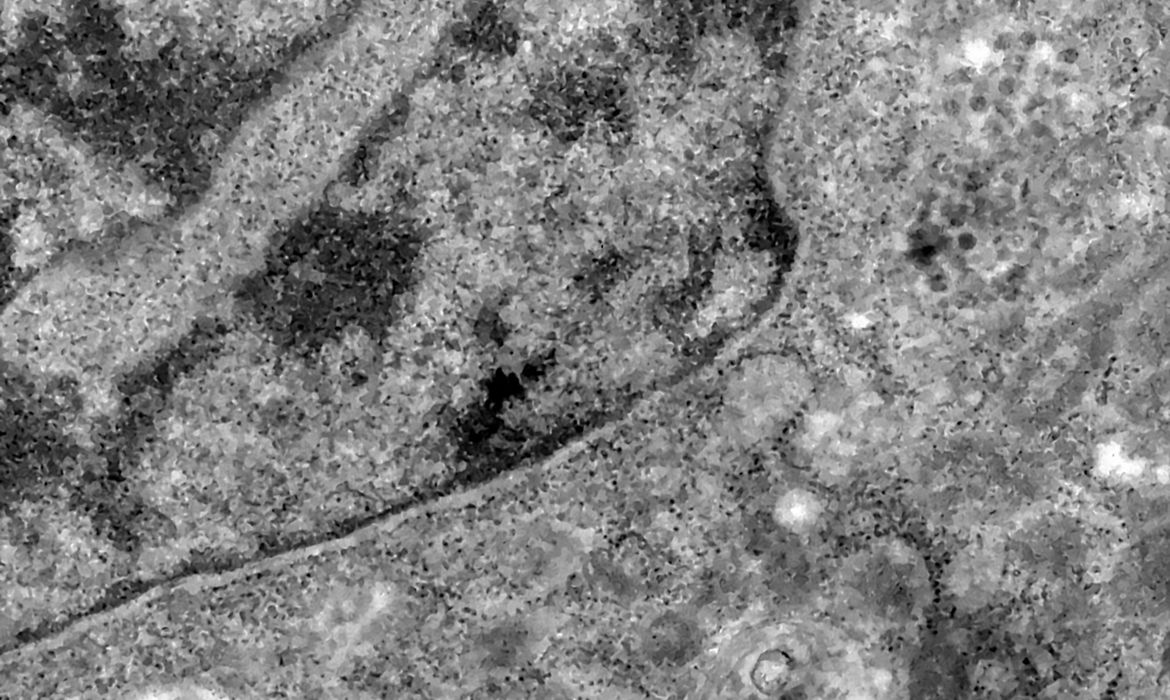

Nos casos analisados, constatou-se que a variante é portadora de dezenas de mutações genéticas que podem afetar os índices de contágio e de letalidade. A OMS, entretanto, afirmou que ainda não há estudos suficientes para afirmar as propriedades da Ômicron, mas que já existem esforços científicos acelerados para estudar as amostras. Um time de cientistas de universidades da África do Sul está decodificando o genoma da Ômicron, juntamente com dezenas de outras variantes do novo coronavírus.

Tulio de Oliveira, diretor do Centro para Respostas e Inovações Epidêmicas da universidade de KwaZulu-Natal, afirmou em coletiva de imprensa que a variante Ômicron possui “uma constelação incomum de mutações”. A variante Delta, por exemplo, possuía duas mutações em relação à cepa original do novo coronavírus, enquanto a Ômicron possui cerca de 50 - 30 delas localizadas na proteína Spike, responsável por infectar células saudáveis, explicou o brasileiro.